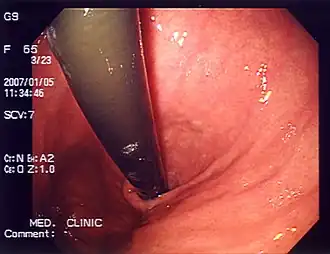

Diagnostic investigations for the evaluation of heartburn include endoscopy and esophageal pH monitoring. GERD is commonly diagnosed based on symptoms of heartburn or regurgitation. Endoscopy may be used to evaluate people who do not respond to treatment for heartburn or those with alarm symptoms such as persistent vomiting, gastrointestinal bleeding, iron-deficiency anemia, involuntary weight loss, difficult/painful swallowing (dysphagia, odynophagia), epigastric mass, family history of esophageal or gastric cancer, and new onset of symptoms in those older than 50 years of age.[23]

Endoscopy is a method used to detect abnormalities in the esophageal lining such as erosive esophagitis and Barrett's esophagus. Biopsies taken during an endoscopy can help assess for other conditions linked to heartburn, such as eosinophilic and lymphocytic esophagitis.[14] The esophageal 24-hour pH test or the multichannel intraluminal impedance-pH test is often performed in those with refractory heartburn who have undergone an endoscopy. High-resolution esophageal manometry (HREM) is the standard test for diagnosing esophageal motor disorders. It helps rule out major motility issues in those with persistent heartburn who have normal endoscopy and pH testing. Motility disorders include achalasia, esophagogastric junction outflow obstruction, diffuse esophageal spasm, jackhammer esophagus, and absent contractility. HREM can also distinguish GERD from conditions like rumination and supra-gastric belching. In some cases, gastric scintigraphy may be used to detect gastroparesis.[24]

Functional heartburn is a burning feeling behind the breastbone, similar to GERD, but without signs of acid reflux, esophageal motor disorders, or mucosal damage on diagnostic tests like reflux monitoring, manometry, or endoscopy. After tests have been performed to rule out other causes of heartburn, functional heartburn is diagnosed according to diagnostic criteria:[25][26]